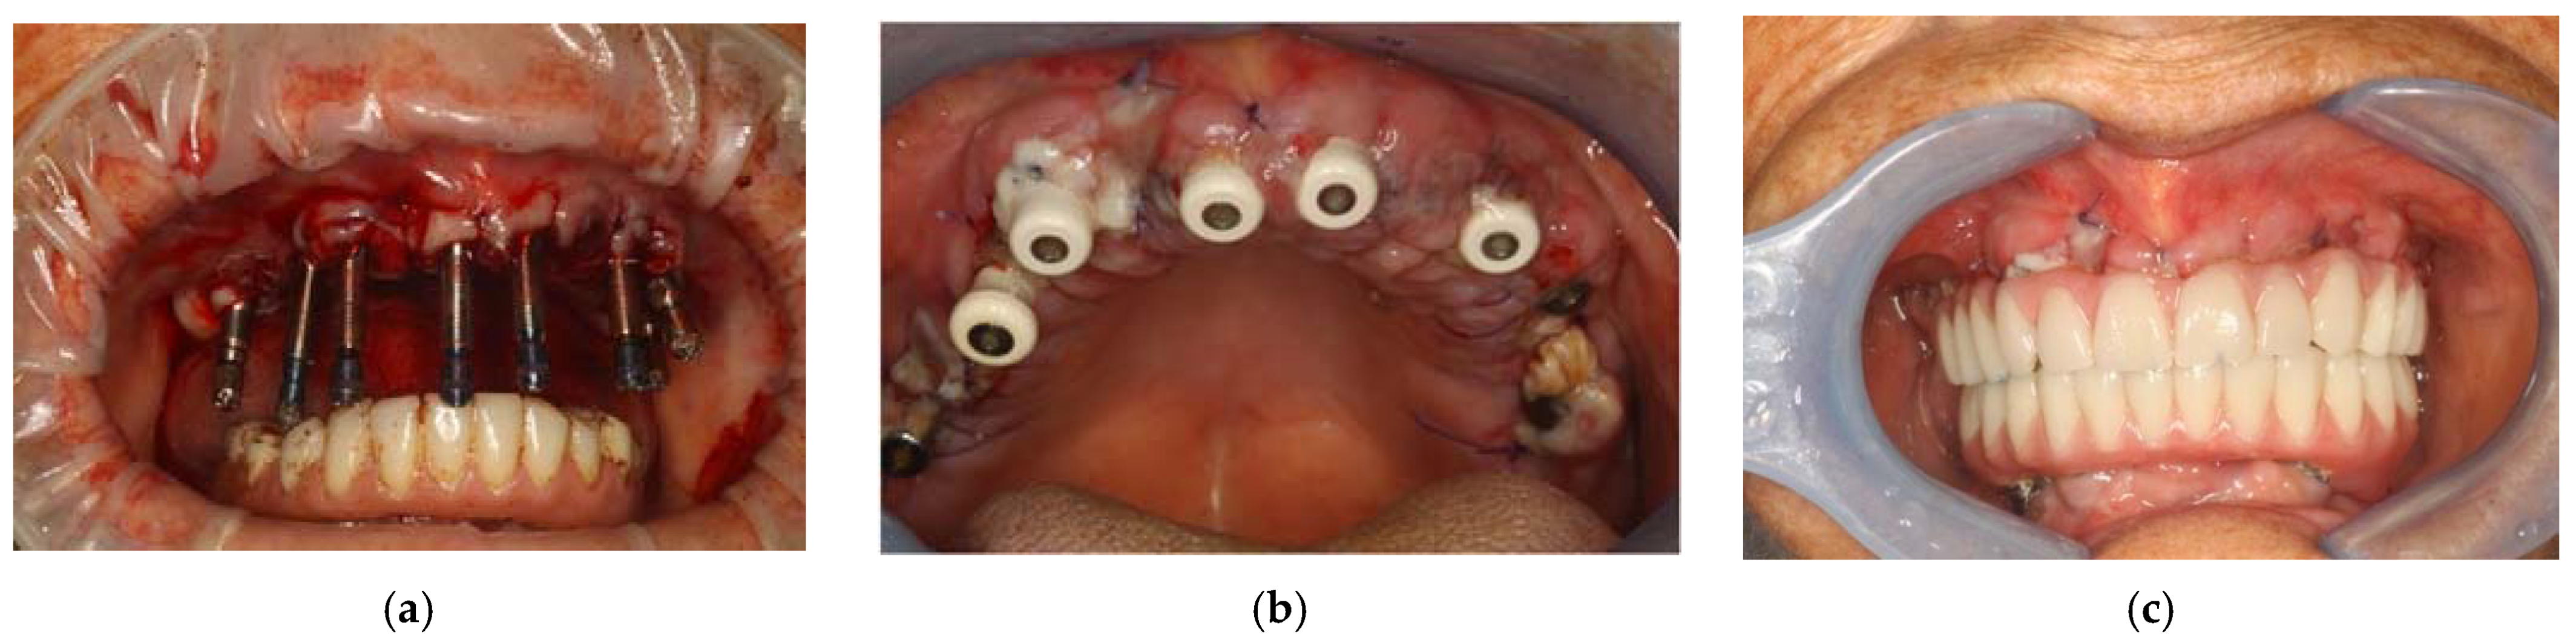

Surgical Procedure